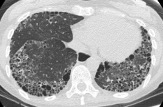

- Chest imaging such as chest X-ray or high-resolution CT scan